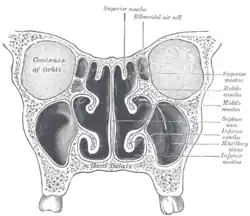

1 obere, 2 mittlere, 3 untere Nasenmuschel

1 obere, 2 mittlere, 3 untere Nasenmuschel

Frontalschnitt durch die Nasenhöhle

Frontalschnitt durch die Nasenhöhle -

Siehe auch nebenstehende Abbildung von Henry Vandyke Carter. Wegen der Spiegelung erkennt man in der rechten Bildhälfte die drei rechten Conchae mit ihren vier Meatus und spiegelsymmetrisch in der linken Bildhälfte die drei linken Conchae mit ihren vier Meatus.